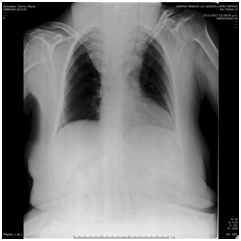

Preoperative tests revealed no nutritional deficiencies. At the first physical examination, the patient is shown with a volume increase in the neck with a neck circumference of 66 centimeters, the largest limited oral opening, a chest x-ray is performed presenting retrosternal goitre with displacement and narrowness of the airway to the left. Therefore, computed tomography is taken, revealing narrowness of the larynx of 7.4x17.09 mm corroborated in the reconstruction of the airway (Figure 2–5), so it was scheduled by general surgery for a thyroidectomy plus tracheostomy.

Figure 2 Imaging depicting tracheal deviation.

Figure 3 Imaging depicting tracheal deviation and compression.

Figure 4 Imaging depicting tracheal deviation.